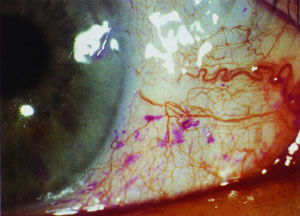

3、胞瞼、白睛不紅不腫,黑睛外觀端好,或見白睛赤脈隱隱,或黑睛有細小星點。